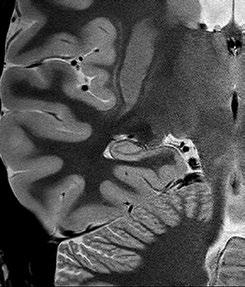

Fig 1: Next generation MRI is being used to gather data on brain tissue volumes Dr. Steve McNally

From this season at Manchester United Football Club, we have started to gather data by using MRI (see fig 1) to measure volumes of brain tissue in specific areas, to monitor for a decrease in volumes over time. If the volumes become unusual or deviate from the norms that we would expect, it may help us identify early changes of CTE that need closer monitoring. This is a new, long-term data gathering study in our cohort of players that has been facilitated with the new next generation MRI3 now in place at our medical centre.

The power of MRI to pick up subtle injuries

Even the smallest injury in elite sports has implications. Having the right diagnostic tool at the peak of its development is vital to diagnosing subtle injuries that could impact player health. Using high resolution MRI therefore helps to identify very minute intra-articular joint injuries, muscle oedema changes or very small fibre tears (see fig 2).

Fig 2: Very small fibre tears identified using high resolution MRI